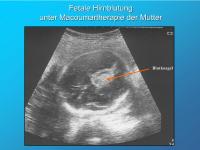

Fetale Hirnblutung unter Macoumartherapie der Mutter

Abbildung 7

Keywords:

Blutkoagel

fetale Hirnblutung

Marcoumartherapie